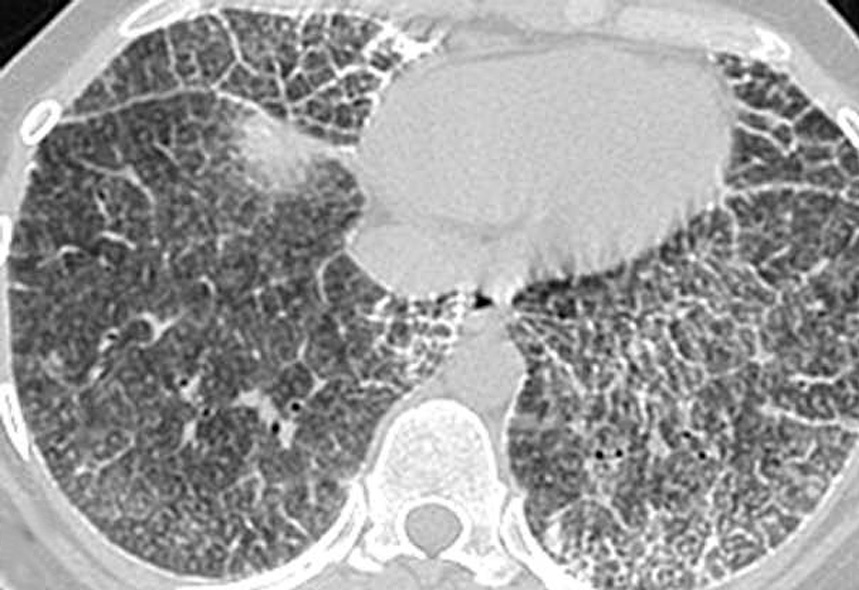

Las imágenes demostraron la presencia de puntiformes y difusas calcificaciones bilaterales, de predominio subpleural, en pleura mediastínica y en los septos interlobulillares. Los segmentos posteriores e inferiores estaban mayoritariamente afectos (fig. 2). También se visualizaron nódulos calcificados a nivel de segmentos anteriores (fig. 2B). El estudio detallado de alta resolución demostró un "patrón en empedrado" o crazzy-paving con marcado engrosamiento de los septos interlobulillares asociado a áreas parcheadas de aumento de la densidad en "vidrio deslustrado" o ground-glass, con mayor afectación de los segmentos posterobasales (figs. 3A y B). A nivel de los lóbulos superiores también se evidencian pequeños quistes subpleurales (fig. 3C).

Fig. 3. Las imágenes tomográficas de alta resolución demuestran la presencia de áreas mal definidas de aumento de densidad en vidrio deslustrado o ground-glass, con moderado engrosamiento de los septos interlobulillares, principalmente en los segmentos anteriores, adoptando en conjunto un "patrón en empedrado" o crazy-paving pattern (A). Secciones inferiores (B) demuestran la mayor afectación de las bases pulmonares. (C) También pueden visualizarse pequeños quistes subpleurales (flechas).